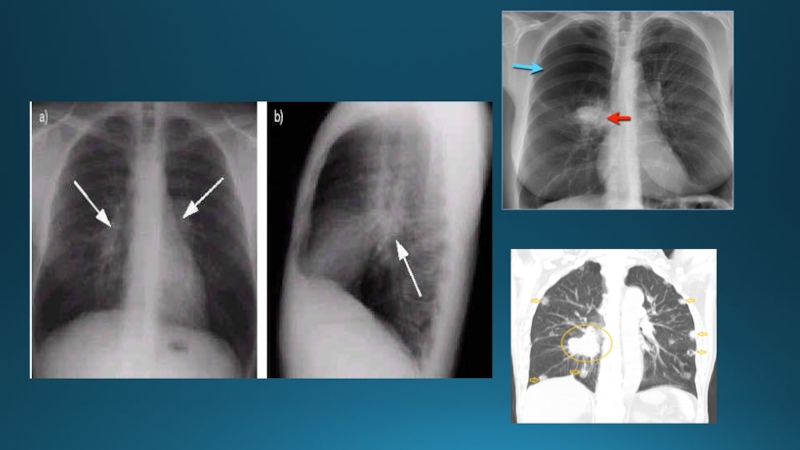

Слайд 44Өкпе түбірінің патологиялық өзгеріс синдромы

Бұл науқас рентгенограммасында өкпе түбірінің өзгерісі,

кеудеішілік лимфа түйін туберкулезіне сәйкес.

Слайд 46Өкпе суретінің патологиялық өзгеріс синдромы

Бұл рентгенограммада өкпе суретінің күшеюі.

Өкпе суретінің патологиялық өзгеріс синдромыБұл рентгенограммада өкпе суретінің күшеюі.

Слайд 47Рентгенограмманың ұлғайтылған фрагменті (оң жақ түбір аймағы). Созылмалы бронхит кезіндегі

өкпе суретінің диффузды күшеюі және «торлануы».

Рентгенограмманың ұлғайтылған фрагменті (оң жақ түбір аймағы). Созылмалы бронхит кезіндегі өкпе суретінің диффузды күшеюі және «торлануы».

Слайд 48Темекі шегетін науқастың өкпе рентгенограммасы қалыңдаған аймақтар мен өкпе суретінің

күшеюі.

Өкпе артерия бұтақтарының ангиографиясы

Темекі шегетін науқастың өкпе рентгенограммасы қалыңдаған аймақтар мен өкпе суретінің күшеюі. Өкпе артерия бұтақтарының ангиографиясы